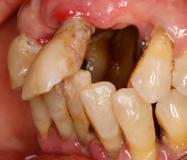

En las fotografías ( Figura 2 ) se observa clase III esquelética, hiperdivergente, la clase III molar derecha y clase que no está determinada, la molar izquierda, clase canina derecha III, clase II canina izquierda, (Figura 3) con la ausencia de los OD 17, 15, 16, 36, 37, 47, el 23 está retenido en palatino, el overjet y overbite están disminuidos, con la línea media inferior desviada, la paciente refiere que ya le habían realizado una cirugía de Lefort IV antes de llegar al CESO.

Figura 2. Frente inicio. Figura 3. Izquierda y derecha intraoral de inicio.

se ve la malposición, apiñamiento con la ausencia de órganos dentarios.